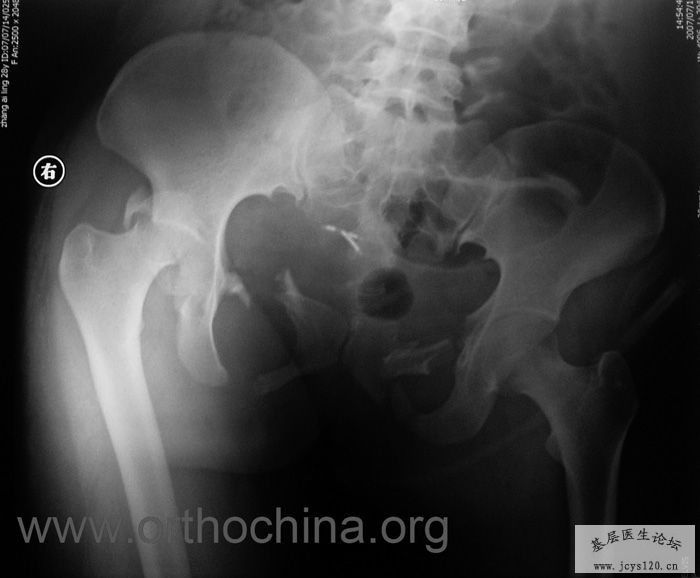

患者,女,28岁,车祸中骨盆轧伤后疼痛功能障碍1小时。查体:休克外貌,烦躁不安。头颈胸腹无异常,脊柱无异常,两下肢血供及感觉正常。骨盆挤压分离试验阳性。阴道、尿道、直肠、腹内脏器无损伤。住院后抗休克、骨牵引及对症治疗1周后,行前后联合入路手术。股骨头骨折复位后用可吸收螺钉固定,骶髂关节、髋臼前后柱、对侧耻骨上下支用骨盆重建钛板固定,术中出血1200ML,手术时间8小时。部分图片如下: